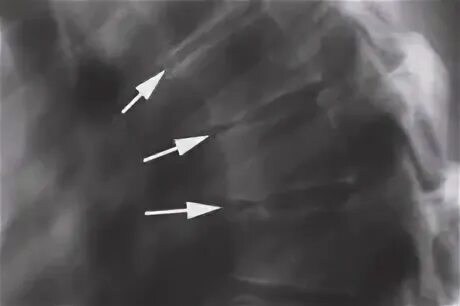

Болезнь шейермана мау код